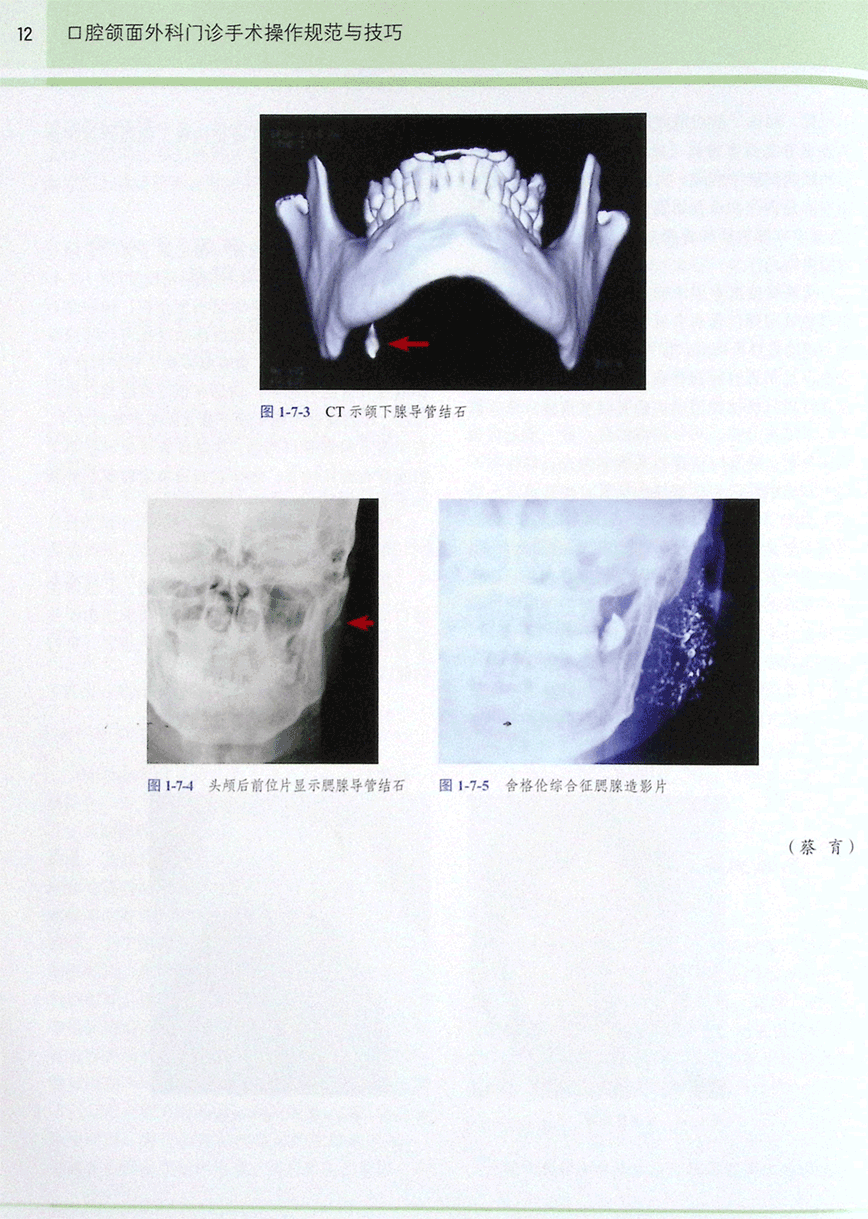

第七节 涎腺疾病患者的术前检查